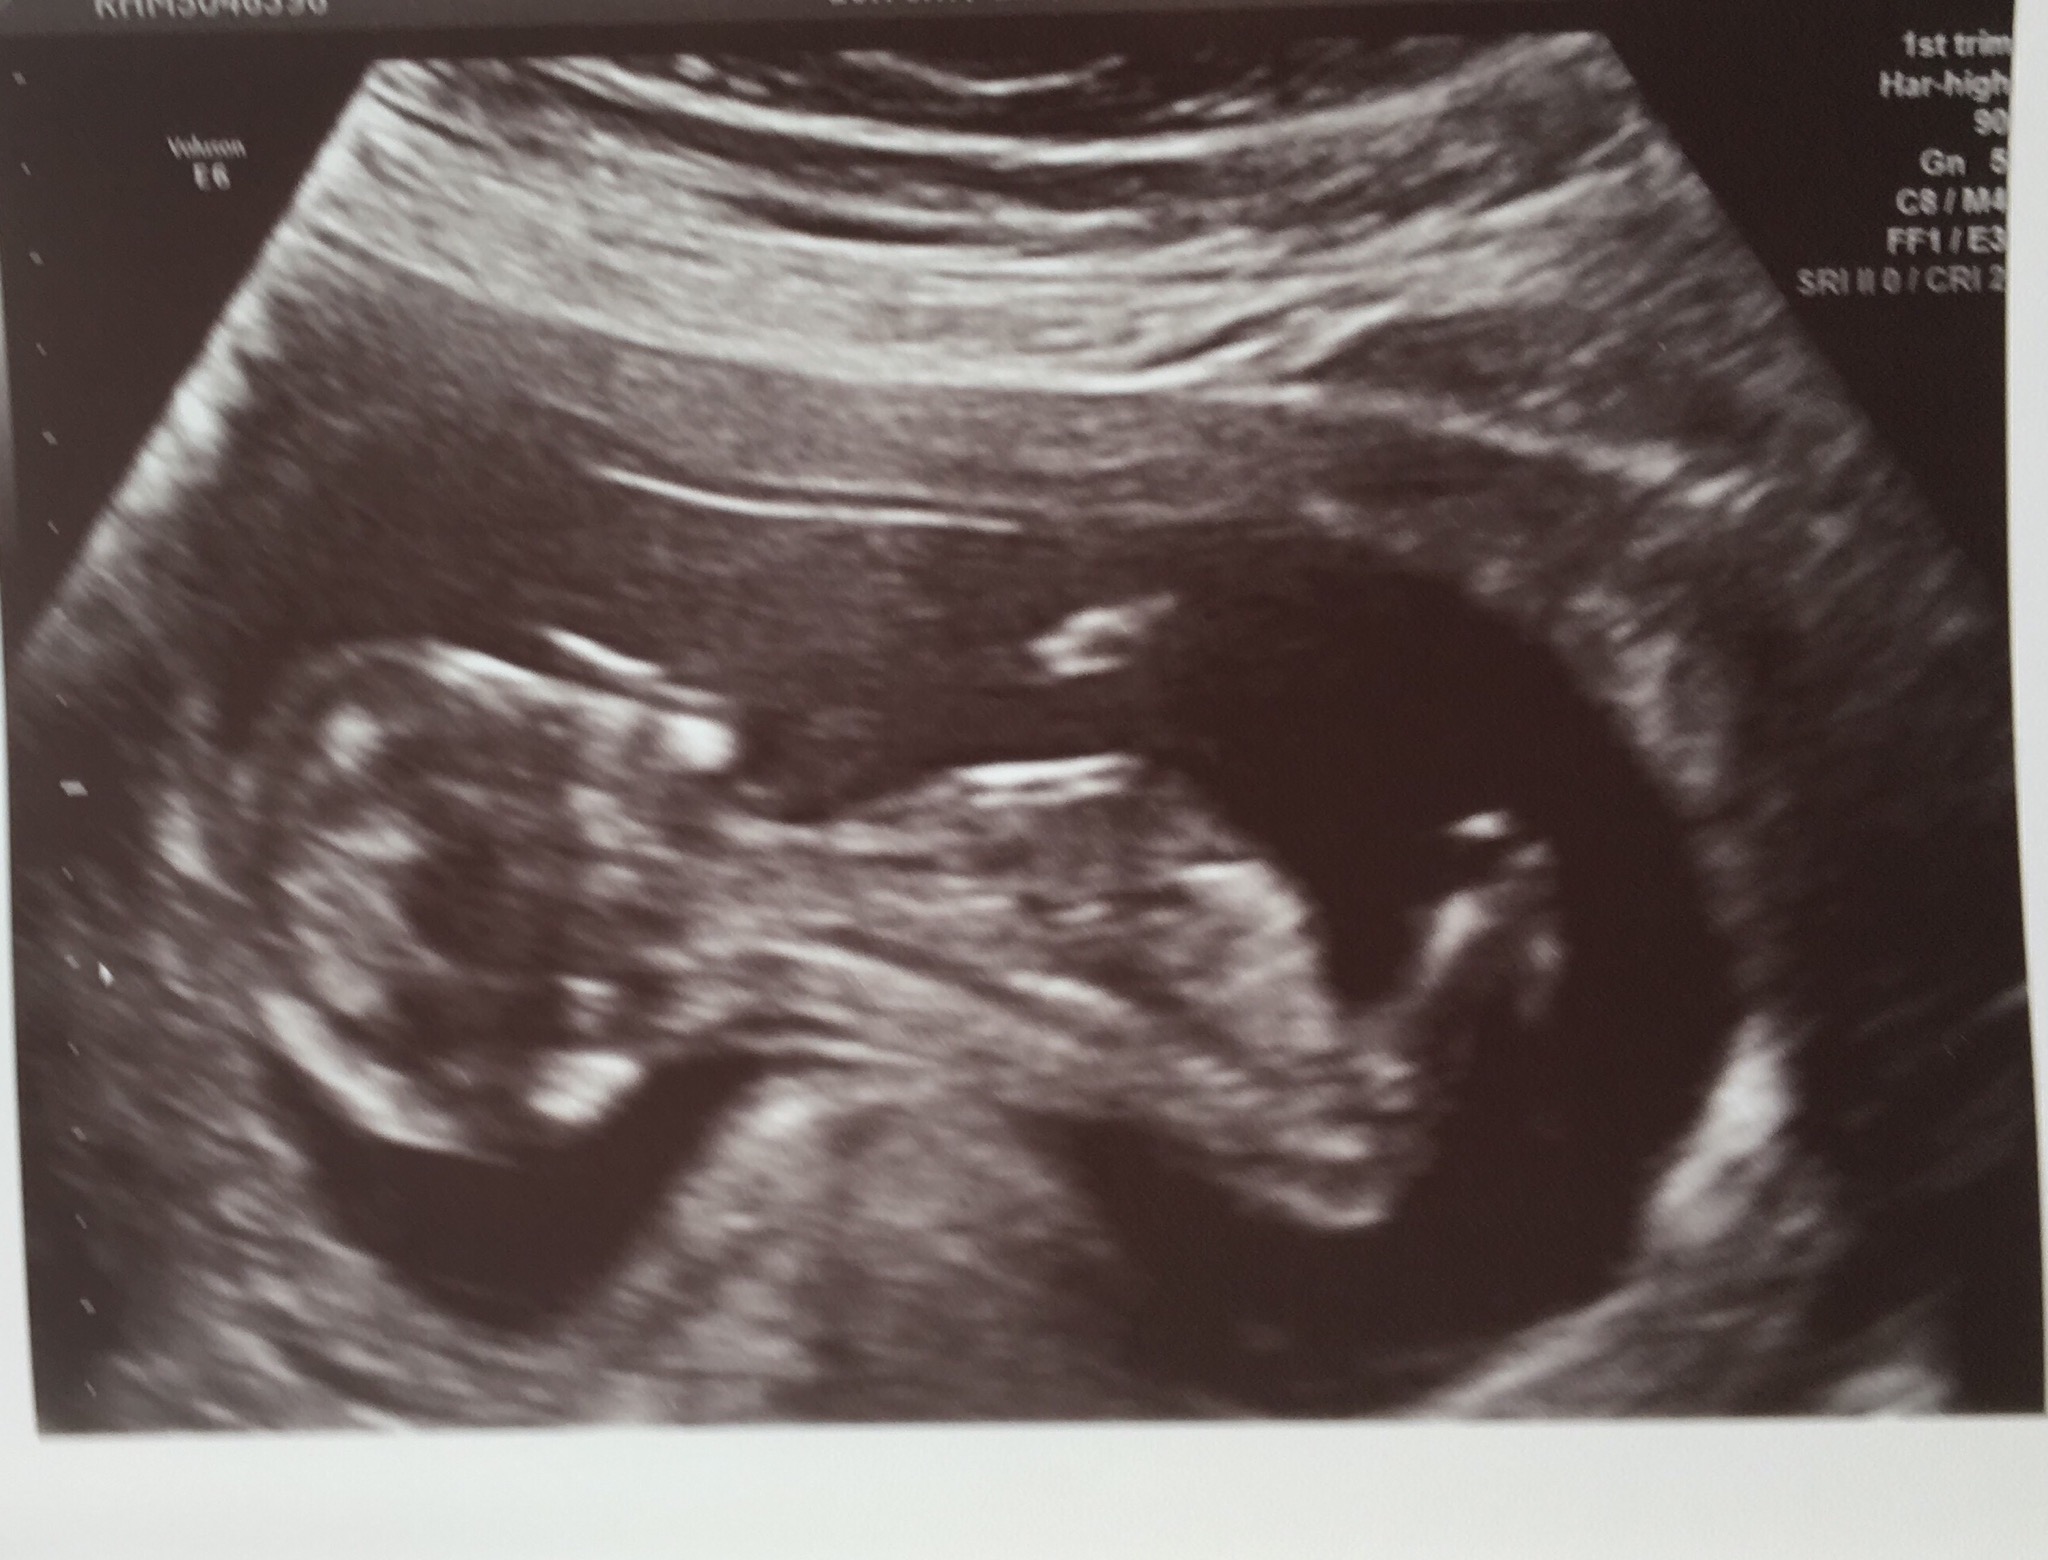

I’ve had both 12 week and 20 week scans and thought I wanted the surprise 3 rd time round but that’s proving more difficult as I approach my 4d scan in Feb. I already have 2 DS and would dearly love a little pink one to complete me but this baby is the last so either way I’m done as financially, spacially and practically we can’t afford anymore.I have thought girl from day one of conception for numerous reasons, timed conception (5-8dpo), feeling very nauseous, strong metallic taste in my mouth which is still present, bad breakouts all of which I didnt have with my boys. I’d be very interested to know what you all think 🤔 Attachment 38554Attachment 38556